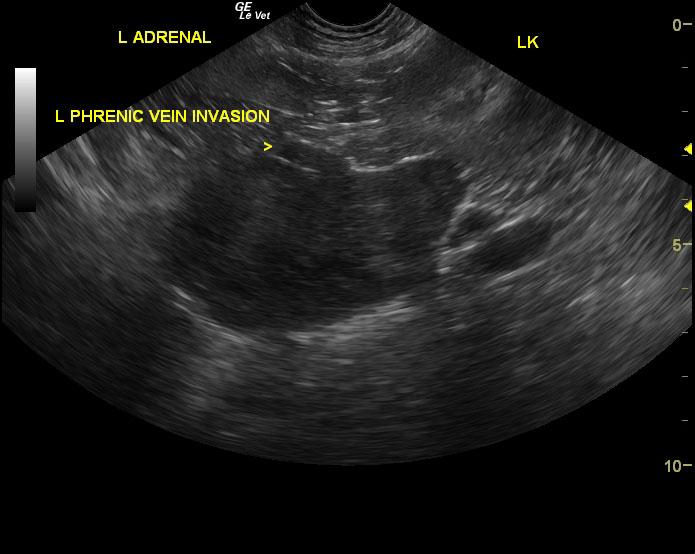

Left adrenal gland mass invading the left phrenic vein. This mass appears to be resectable and is most consistent with adrenal gland carcinoma. Surgical consultation is recommended as well as three view chest radiographs and blood pressure measurements.

The right adrenal gland was isoechoic to surrounding fat. It measured 2.1 x 0.9 cm. The left adrenal gland comprised a 7.9 x 5.3 cm strongly vascular mass noted on power flow Doppler. Invasion into the left phrenicoabdominal vein was noted. However, the vena cava was not invaded at this time.